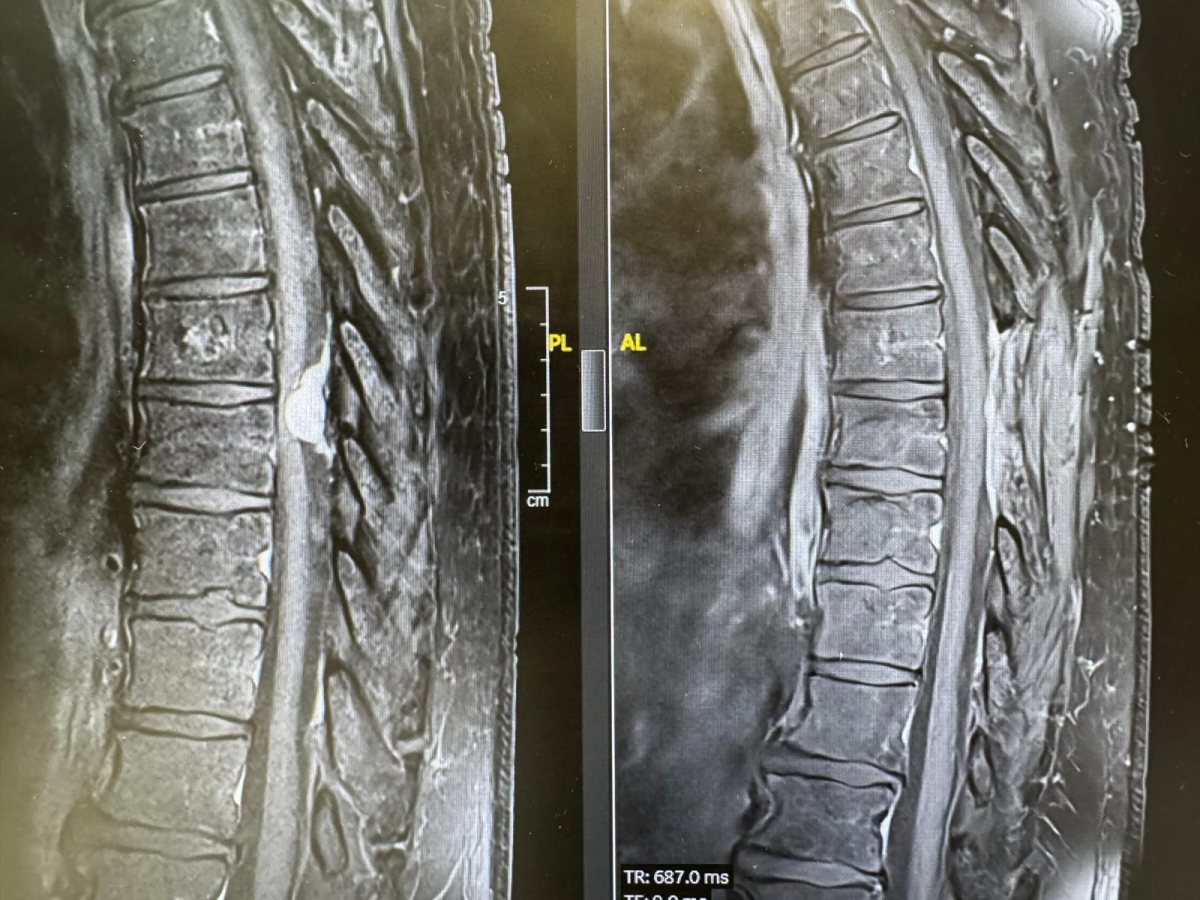

מניגיומה של עמוד השדרה הוא גידול שפיר שנמצא בתוך הקרומים של עמוד השדרה. הגידול, שנפוץ בעיקר בקרב נשים בגילים מבוגרים יותר, גורם ללחץ על עמוד השדרה ועל העצבים ומוביל לתסמינים שונים בידיים וברגליים, ובהם, נימול, חולשה בגפיים, בעיות בהליכה ואף לשיתוק.

רק כשהגעתי לשערי צדק הבינו, לאחר שד"ר מרדכי לין מהמחלקה הניורולוגית עשה לי בדיקת MRI, שיש לי גידול שפיר בעמוד השדרה בגודל של כדור טניס. הגידול הוסר בניתוח ומיד לאחריו התחלתי להרגיש שיפור והצלחתי להזיז את רגל שמאל. בזכות הצוות המדהים של הרופאים והאחיות בשערי צדק, אני מצליחה לעשות היום משהו שלא יכולתי בעבר. מעולם לא קיבלתי יחס כזה מצוות רפואי - הם פשוט מלאכים, אין לי מילה אחרת, לא רציתי לעזוב את בית החולים מרוב שהחוויה הייתה טובה".